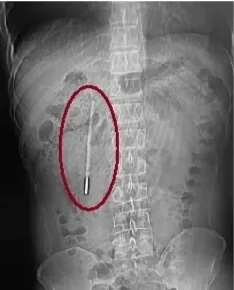

温州网讯 12岁时误吞的一根体温计,竟在肚子里“潜伏”了整整20年。近日,温州医科大学附属第一医院医护团队用内镜从患者王先生的十二指肠处取出体温计。

32岁的王先生最近腹部消化不好,前往温医大附一院龙港院区就诊。该院区医生对其做腹部CT检查,发现其十二指肠处有异物,怀疑是水银体温计,前端已抵在肠壁上,随时可能引发穿孔、大出血等严重后果。追问病史后得知,这根体温计是王先生12岁时不慎误吞的,当时因害怕不敢告知家长,而其身体没出现异样,也就没把这件事放在心上。此次就诊前,他未做过体检。

该院内镜中心医护团队开展内镜下取物操作。由于体温计滞留时间长、位置深,且毗邻胆管胰管,操作空间狭窄,稍有不慎便会损伤肠壁。该团队在相应器械的辅助下精准定位,用圈套器套住体温计一端,缓慢轻柔提拉,经20分钟努力终于将其完整取出,取出的体温计除刻度消失外,外观完好。